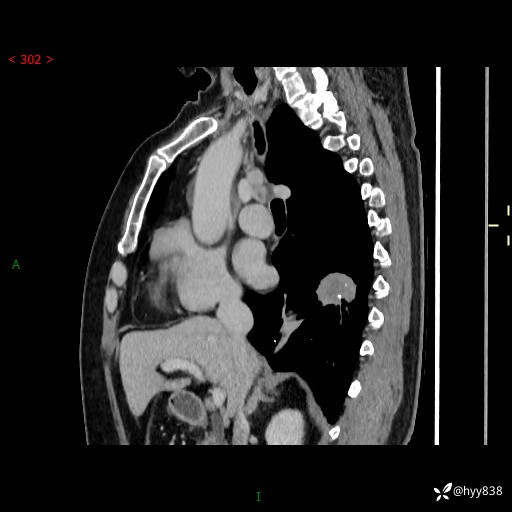

简要病史:患者1月余前无明显诱因出现咳嗽咳痰,痰液以黄色脓痰为主,无发热、头痛头晕、胸闷气喘、腹胀腹泻等不适,于当地卫生院行输液治疗1周后症状缓解,5天前再发咳嗽咳痰,于当地卫生院输液2天,症状稍缓解,3天前突发头晕、呕吐,遂于2023-11-08在当地第五人民医院就诊,行胸部CT提示右下肺占位性病变。患者现为求进一步诊治来我院就诊,门诊以“肺肿物”收住我科。 患者自起病来精神、食欲、睡眠尚可,大小便正常,体力、体重无明显变化。

临床诊断:肺肿物

胸部CT肺窗(平扫外院)